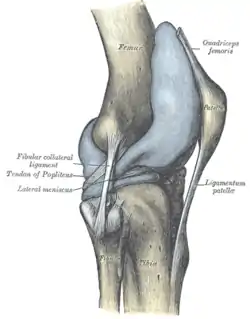

Left knee-joint from behind, showing interior ligaments. Capsule of right knee-joint (distended). Lateral aspect.

Capsule of right knee-joint (distended). Lateral aspect. Anterior and lateral view of knee.